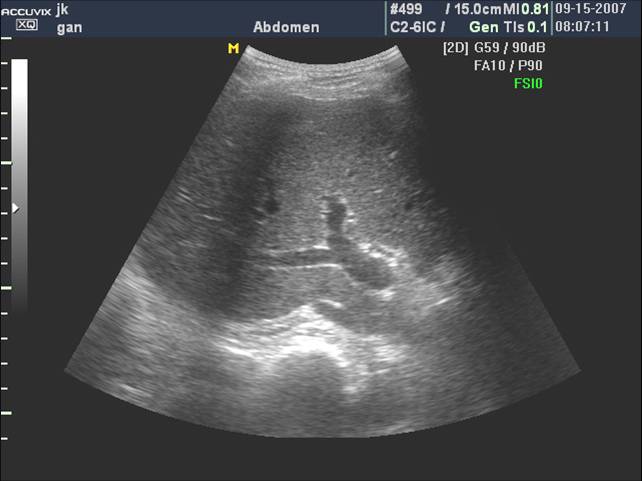

(二)门静脉

门静脉主干是由肠系膜上静脉和脾静脉在胰颈背侧汇合而成,居于胆总管和肝动脉之后。

门静脉从第一肝门开始,分左右两大支。左支沿横沟向左侧横行行走,名左支横段,待抵达左内、外叶交界处,折向足端走,与横段垂直,形成独特的“C”形结构称矢状段, 末端稍膨大称囊部,与肝圆韧带相连,后者为脐静脉闭锁后的残迹。

门静脉左干横部、矢状部及左内叶支和左外叶上、下段支的空间投影图像呈“工”字形:

门静脉右支较短,约1.5cm左右,向右水平走行分成右前支和右后支,前支和后支分别再分成上段支和下段支:

门静脉右干及分支,当探头沿着门静脉主干右上方移动可显示右干,其远端“Y”型分叉:

门静脉主干及右支长轴和胆囊长轴呈空间"垂直",立体投影空间排列呈"飞鸟样":